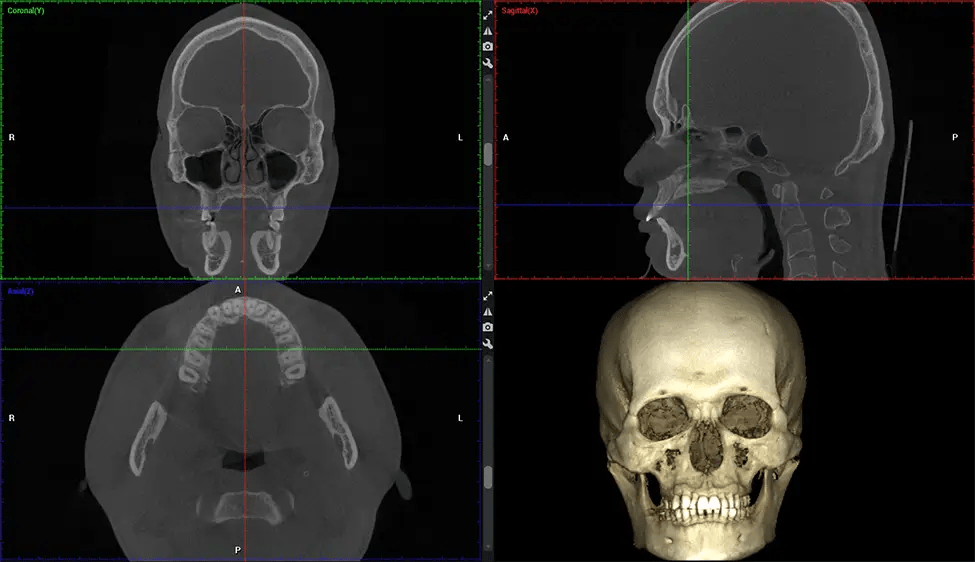

Esta exploración 3D, llamada tomografía computarizada de haz cónico, le brinda a su dentista una imagen más completa de su anatomía bucal y sus procesos patológicos que una radiografía tradicional. A diferencia de las radiografías convencionales, que capturan una imagen 2D de la boca desde varios ángulos, una exploración 3D toma varias radiografías digitales para una imagen. Proporciona una vista completa de la mandíbula, los dientes, los nervios y los tejidos blandos. Esta vista mejorada permite a los dentistas detectar problemas menores que no son visibles en las exploraciones 2D tradicionales, como muelas del juicio impactadas o fracturas óseas en la cavidad sinusal.

Existen muchos beneficios al utilizar la tecnología CBCT, especialmente en comparación con el formato tradicional de rayos X 2D. Una de las ventajas más importantes de las exploraciones CBCT es que proporcionan mucha más información que las radiografías tradicionales. Una exploración le permite a su dentista ver imágenes desde todos los ángulos de su mandíbula y boca, incluidos los senos nasales, la cavidad nasal, los pómulos y otras áreas circundantes. Esta información adicional ayuda a su dentista a elaborar un plan de tratamiento integral que aborde todos los aspectos de su salud bucal.

Planmeca Viso G7 CBCT (Cone Beam CT Scan) está diseñado para superar las demandas de los líderes de la industria, los especialistas y las grandes instituciones. Tiene un gran sensor de ø25×30 cm con cuatro cámaras integradas. Puede capturar tamaños de volumen ilimitados, desde ø3×3 cm hasta ø30x30cm, capturando el casquete escutelario a través de C7 en la columna cervical. Planmeca Viso G7 ofrece el escaneo de volumen único más grande de la industria de ø30×19 cm. Está preparado para manejar modalidades de imágenes avanzadas como la tecnología Planmeca ProFace® y Planmeca 4D™ Jaw Motion. El soporte occipital para la cabeza permite una visión sin obstáculos del tejido facial.